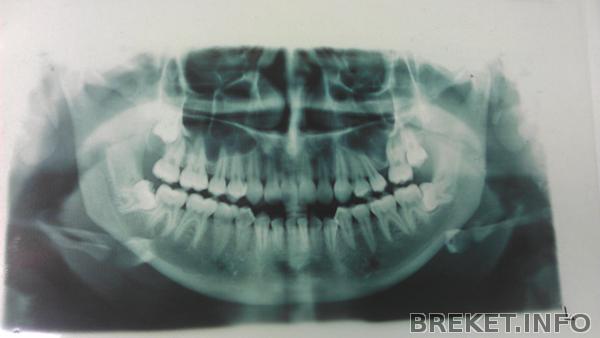

Попросила еще сфоткать старый ОПТГ (Ennelyne, Натали, специально для тебя, ты просила) и направление на новый, сегодня сделала. Думала, что все будет получше

8-ки вылезли на НЧ, но они наклонены, а на ВЧ одна вылезла (справа на снимке, она немного опустилась), в другая еще нет, но по ОПТГ видно, что она тоже опустилась немного

А восьмёрки удалять не планируется? Левая как-то совсем нехорошо лежит...